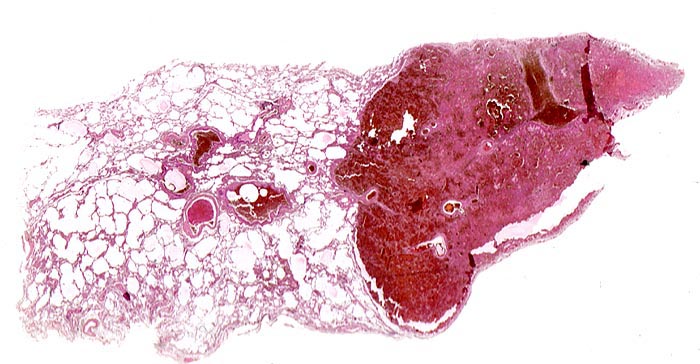

Hämorrhagischer Lungeninfarkt

Makroskopisch bilden sie ein Dreieck mit der Basis an der Pleuraoberfläche, sind leicht erhaben, dunkelrot gefärbt und induriert. Innerhalb von 48 Stunden beginnen die Erythrozyten zu zerfallen und der Infarkt wird von aussen her narbig organisiert.

- Scharf begrenzte dreiecksförmige hämorrhagische Nekrose des Lungenparenchyms.

- Alveolen gefüllt mit zerfallenden Erythrozyten, Kerntrümmern und Fibrin.

- Lungengerüst erhalten im Randbereich der Nekrose, nicht mehr erkennbar im Zentrum.

- Abgeblasste Zellkerne in der Nekrosezone.

- Pulmonalarterienast mit nicht wandhaftendem Thrombembolus am Rand des Infarktes.

- Frischblut im Lumen des begleitenden Bronchiolus.